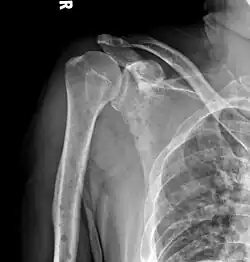

The diagnostic examination of a person with suspected multiple myeloma typically includes a skeletal survey. This is a series of X-rays of the skull, axial skeleton, and proximal long bones. Myeloma activity sometimes appears as "lytic lesions" (with local disappearance of normal bone due to resorption) or as "punched-out lesions" on the skull X-ray ("raindrop skull"). Lesions may also be sclerotic, which is seen as radiodense.[76] Overall, the radiodensity of myeloma is between −30 and 120 Hounsfield units (HU).[77] Magnetic resonance imaging is more sensitive than simple X-rays in the detection of lytic lesions. An MRI may supersede a skeletal survey, especially when vertebral disease is suspected. Occasionally, a CT scan is performed to measure the size of soft-tissue plasmacytomas. Nuclear Medicine Bone scans are typically not of any additional value in the workup of people with myeloma (no new bone formation; lytic lesions not well visualized on nuclear bone scan).